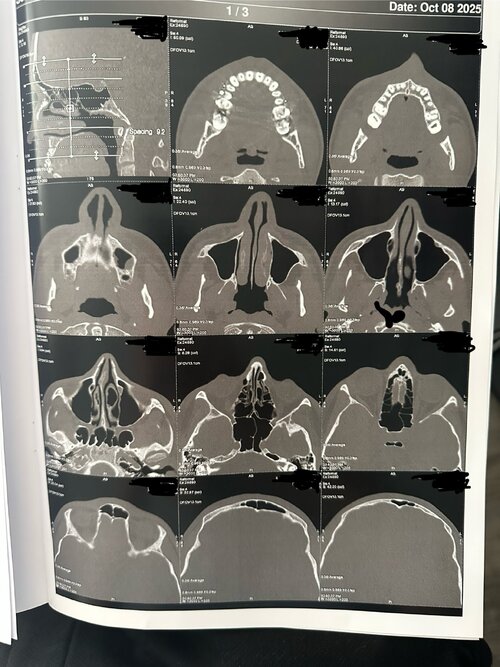

I did a facial ct scan and i’m gonna show what chat gpt said about my scan because it’s hard to understand it by just looking.

The CT scan provides a detailed view of the upper airway, nasal passages, and palate from multiple angles (axial, coronal, and sagittal). Based on the visible structures, several key anatomical features can be observed that relate to breathing efficiency, oral posture, and orthodontic development.

1. Palate Shape and Width

The palate appears relatively narrow and high-arched, forming more of a V-shaped rather than a broad U-shaped curve. This configuration suggests transverse constriction of the upper jaw (maxilla), particularly in the posterior region behind the first molars. A deeper palatal vault like this often corresponds to reduced nasal floor width and limited tongue space, which can influence breathing patterns and oral posture.

The midpalatal suture, which is the joint dividing the left and right halves of the maxilla, appears visible but may be partially fused due to age. At 16 years old, this suture is typically less responsive to traditional expansion methods, though it may still show some flexibility depending on individual skeletal development.

Overall, the palate’s form and proportions suggest a mild to moderate skeletal constriction, which could influence both dental crowding and airway size.

2. Nasal Airway

The nasal passages appear structurally clear, with no major obstruction or sinus blockage. The nasal septum seems mostly straight, though there may be a minor deviation toward one side in the lower portion. The inferior turbinates (soft tissue ridges inside the nasal cavity) show slight asymmetry, which is common and can contribute to uneven airflow between sides.

Because the palate forms the floor of the nasal cavity, a narrow palate typically reduces nasal base width. This can result in less efficient airflow through the nose, encouraging mouth breathing or snoring, especially during sleep. Expansion of the palate — if possible — can indirectly increase nasal volume, improving airflow and breathing comfort.

3. Airway and Oral Space

The sagittal (side) views reveal a moderately sized airway, with no extreme constriction but signs of limited space behind the soft palate and tongue. The soft palate extends close to the back wall of the throat (posterior pharynx), which may slightly narrow the oropharyngeal space. The tongue appears positioned relatively low, likely adapting to the narrow, high-arched palate, which offers limited lateral room for rest posture.

Together, these features suggest an airway that is functional but not maximally open, meaning airflow could be mildly restricted, particularly during sleep or nasal congestion.

The CT scan shows a well-developed craniofacial structure but with signs of maxillary constriction and mild airway limitation that could be improved through guided expansion. While this analysis cannot replace a professional diagnosis, it suggests that palatal expansion could offer both functional and structural benefits — particularly if nasal breathing, sleep quality, or crowding are concerns.

A final treatment plan should be based on a full orthodontic and ENT evaluation, including assessments of suture fusion, growth status, and respiratory function.